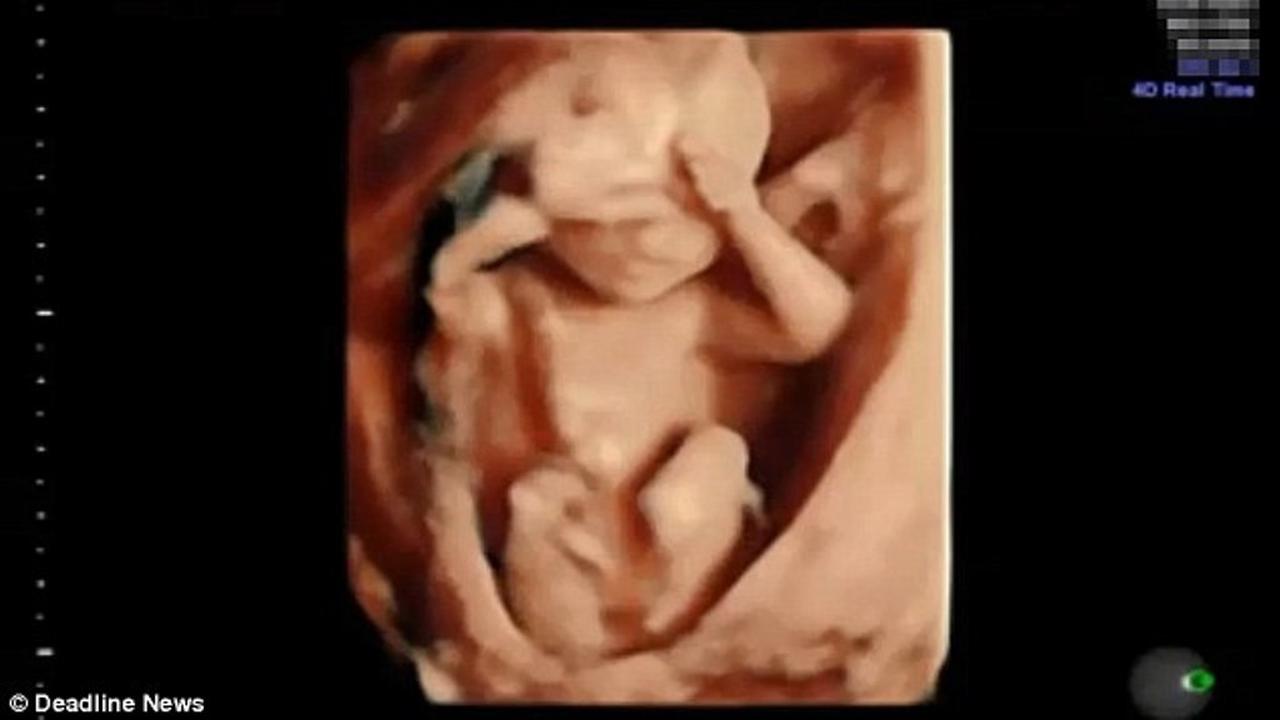

Liputan6.com, London - Pemandangan menakjubkan terlihat dalam video hasil USG bayi berusia 16 minggu ini. Pada rekaman tersebut, ia seolah-olah melambaikan tangan kepada orangtuanya dan bermain cilukba.

Dari gambar hasil USG 4 dimensi itu, terlihat jelas sang bayi mengangkat tangan kirinya dan membuat gerakan melambai. Janin yang diperkirakan lahir pada 9 Juli 2017 itu juga menempatkan kedua tangannya di depan mata, lalu membukanya seperti tengah bermain cilukba.

"Begitu menakjubkan, ia bermain cilukba dalam video, menutup mata dengan tangan dan membukanya," ujar Cheryl.

"Ketika scanning terjadi, dia (bayiku) menggeliat dan aku bisa merasakan dia menarik-narik. Brilian. Dia sangat aktif. Ini luar biasa, Anda dapat melihat semua rincian seperti hidung dan bibirnya."

Berikut ini rekaman menakjubkan USG bayi tersebut: